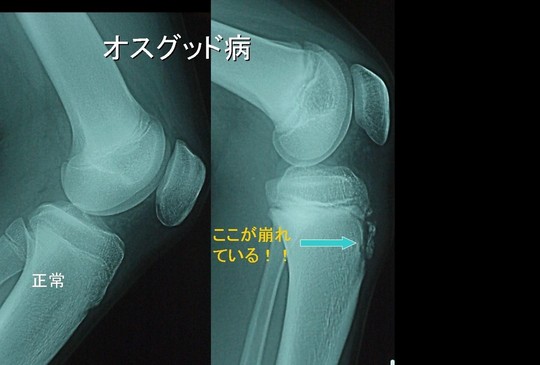

オスグットシュラッター

小学校高学年から中学生のお子さんが、積極的なスポーツ活動をしているうちに、膝の前面(脛骨粗面部・けいこつそめんぶ)に痛みや骨の隆起を訴えます。

その多くはオスグッド病と呼ばれる10代前半に好発する代表的な骨端症(成長期に起きる骨の病変)で、脛骨粗面の骨端軟骨に分離や遊離(骨が一部はがれる事)が生じる障害です。

発生原因には色々な説がありますが現在ではスポーツなどによる"使いすぎ症候群"の一つされ、非常に広い意味での疲労骨折と考えても良いと思います。

膝を伸ばす筋肉である大腿四頭筋(太ももの筋肉)は、膝蓋骨(お皿と呼ばれる骨)と膝蓋靱帯(お皿の下のすじ)を介し脛骨粗面に付着しています。

したがってランニングやジャンプ動作により大腿四頭筋が収縮すると、膝蓋靱帯をとおして脛骨粗面に牽引力が繰り返しかかる事により骨端軟骨に隆起や剥離が起きます、これがオスグッド病です。

診断は、痛みの部位とレントゲン写真により容易にできます。治療は、痛みの程度やスポーツ時の障害の程度により異なります。